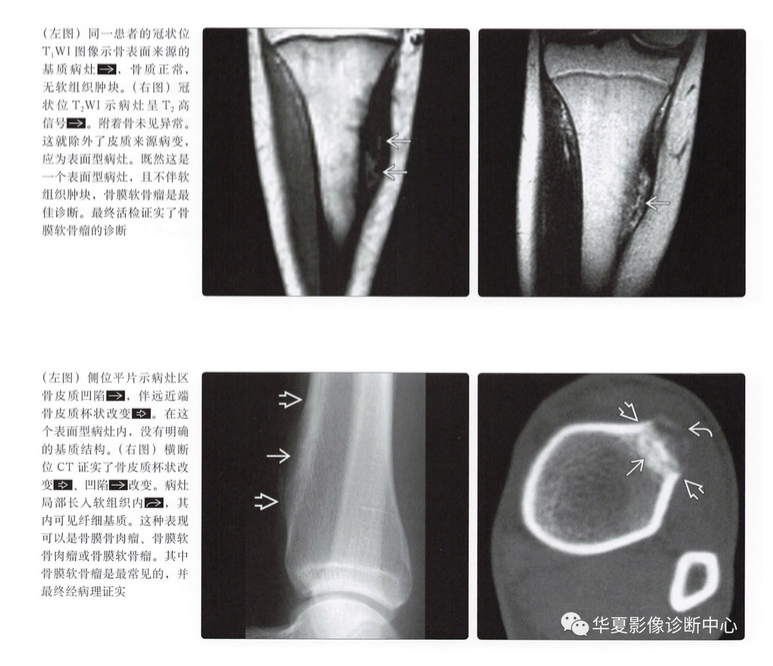

平片表现

- 骨皮质扇形凹陷

- 硬化边

- 致密性骨膜反应,尤其是在病灶近端、远端

- 病灶远端、近端骨皮质杯状改变

- 基质钙化(75%)

- 软组织肿块

CT表现

- 与平片表现类似

- 可以更好地显示软骨基质和扇形凹陷